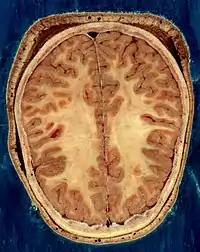

- Del Proyecto "Humano Visible" (Visible Human Project de la Biblioteca Nacional de Medicina de Estados Unidos. En este proyecto, dos cadáveres humanos (de un hombre y una mujer) fueron congelados y luego cortados en láminas delgadas, que fueron fotografiadas y digitalizadas individualmente. Esta sección está tomada a una pequeña distancia de la parte superior del cerebro, y muestra la corteza cerebral (la capa celular plegada al exterior) y la sustancia blanca subyacente, que consiste en tramos de fibra mielinizada que viaja hacia y desde la corteza cerebral.